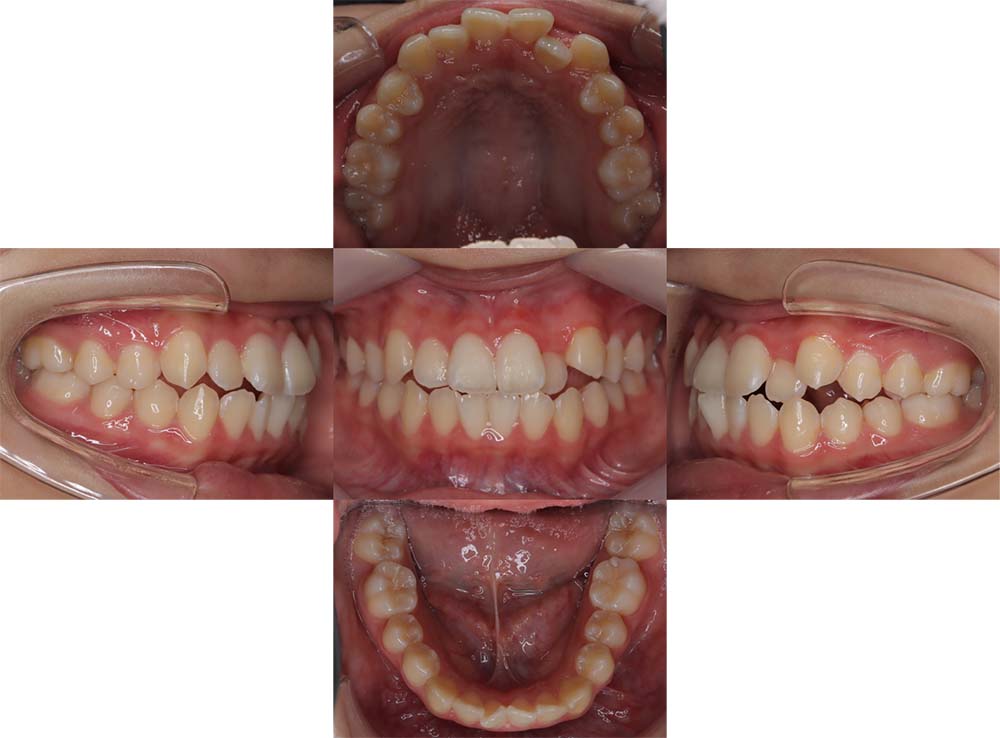

症例01

| 主訴 | 歯並びがガタガタしている。 |

| 診断名あるいは主な症状 | 叢生 |

| 年齢/性別 | 22歳・男性 |

| 矯正ステージ | 大人の矯正治療 |

| 治療方法 | ワイヤー矯正 |

| 抜歯部位/抜歯有無 | 非抜歯 |

| 治療内容 | 上顎大臼歯の遠心移動により前歯のガタガタを排列スペースを獲得し全顎的な排列を行った。 |

| 費用 | 85万円程度(2025.10時点の料金となります。) ※矯正基本料金、審美ブラケットを含む |

| 治療期間 | 2年4ヶ月 |

| 主なリスク・副作用 | 痛み、歯根吸収、歯肉退縮、虫歯、後戻り |